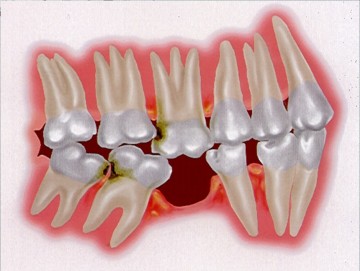

患者許小姐,左下第二小臼齒,因為深度蛀牙,因而牙齒被拔除(圖一、圖二、圖三),患者由於是一位高二學生,深怕缺牙久了若不處理,鄰牙可能倒過來(圖四),但若以傳統假牙修復,還需再磨完整的自然牙(圖五),經轉診至本診所尋求人工植牙。

圖四 |